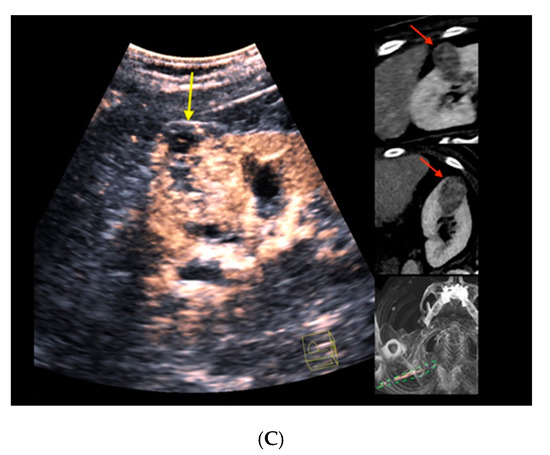

Figure 2 depicts the morphological correlates from CT/CEUS-fusion imaging of a clear-cell RCC. An overview of the findings from cross-sectional imaging (CT/MRI) and corresponding correlates by fusion imaging of the included renal liver lesions is depicted in Table 2.

Figure 2.

Real-time CT-/CEUS-fusion imaging of a complex renal cystic lesion. (A) Known complex renal cystic lesion with indicated septations and solid components in the right kidney from previous contrast-enhanced CT (left, red arrow) is displayed in a side-by-side mode with native B-mode (right, yellow arrow) by a high-end ultrasound system. (B) Additional Color Doppler did not reveal hypervascularization of the lesion (yellow arrow). The software interface of the ultrasound device showed four different images: the real-time Color Doppler image (left, maximized), the CT imaging dataset in sagittal (upper right) and axial (middle right) reformation (lesion marked by red arrows), and a real-time 3D navigation of the Fusion Imaging (lower right). (C) Contrast-enhanced ultrasound allowed for visualization of early arterial microperfusion of solid components of the lesion, implicating malignancy (left, maximized), (lesion marked by red arrows in corresponding CT images). The patient underwent partial nephrectomy. Histopathology, finally, revealed underlying clear-cell renal cell carcinoma.